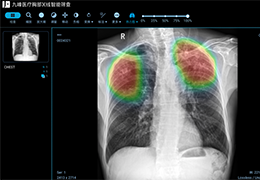

ART-Plan™ Artificial Intelligence Contouring